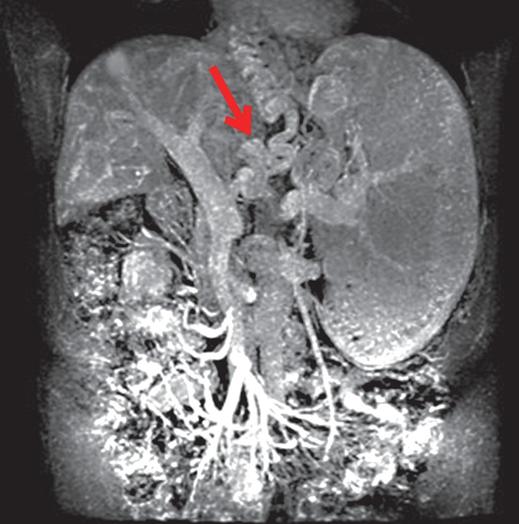

+ Tăng áp lực tĩnh mạch cửa với biểu hiện triệu chứng nôn ra máu và lách lớn (chủ yếu do S. mansoni, S. japonicum);

Hình 9